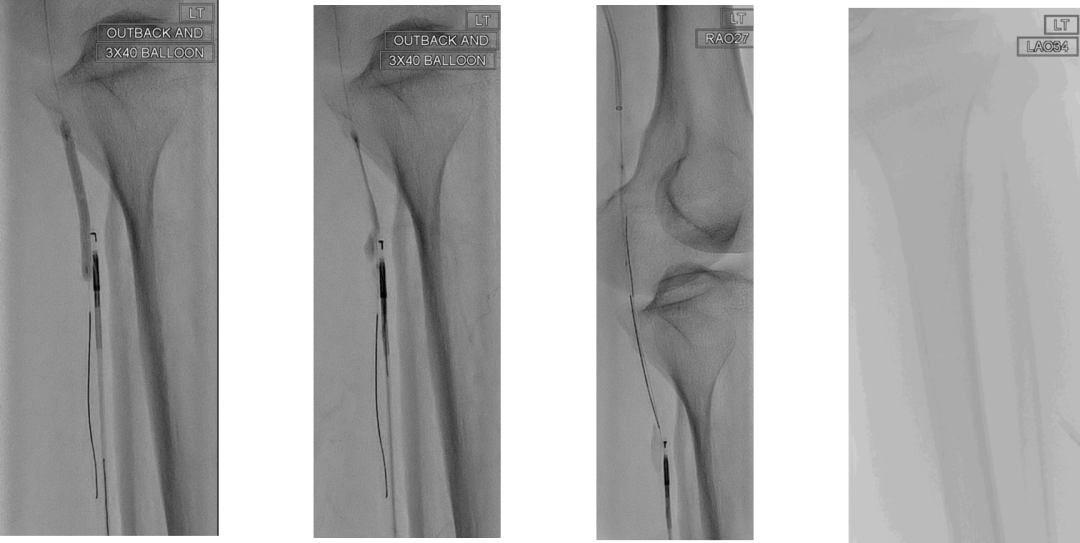

病例示例与技术支持

研究展示了逆行再通中几种高级技术的应用:

Presto技术:通过逆行插入的指引导管辅助,完成治疗。

靶向球囊辅助再入技术(如Outback设备):在顺行球囊标记的引导下,从逆行方向进行精准的真腔再入,高效解决内膜下开通后的对接难题。

这些技术是达成高成功率的重要保障。

CASE 2: